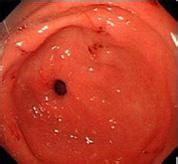

萎缩性胃炎是由于胃黏膜受到反复损伤,导致固有腺体萎缩或消失而形成,对人体的危害非常严重,如果不及时治疗,很可能并发胃溃疡、出血,甚至恶化成癌。

6.胆汁或十二指肠液反流:由于幽门括约肌功能失调或胃空肠吻合术后,胆汁或十二指肠液可反流至胃内,并破坏胃粘膜屏障。促使H+及胃蛋白酶反散至粘膜内引起一系列病理变化,从而导致浅表性胃炎,并可发展为萎缩性胃炎。